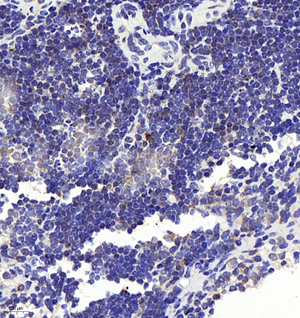

![]() | Immunohistochemistry of paraffin embedded mouse spleen using CD8A (GB11068-1) at dilution of 1:200 (400x lens) |